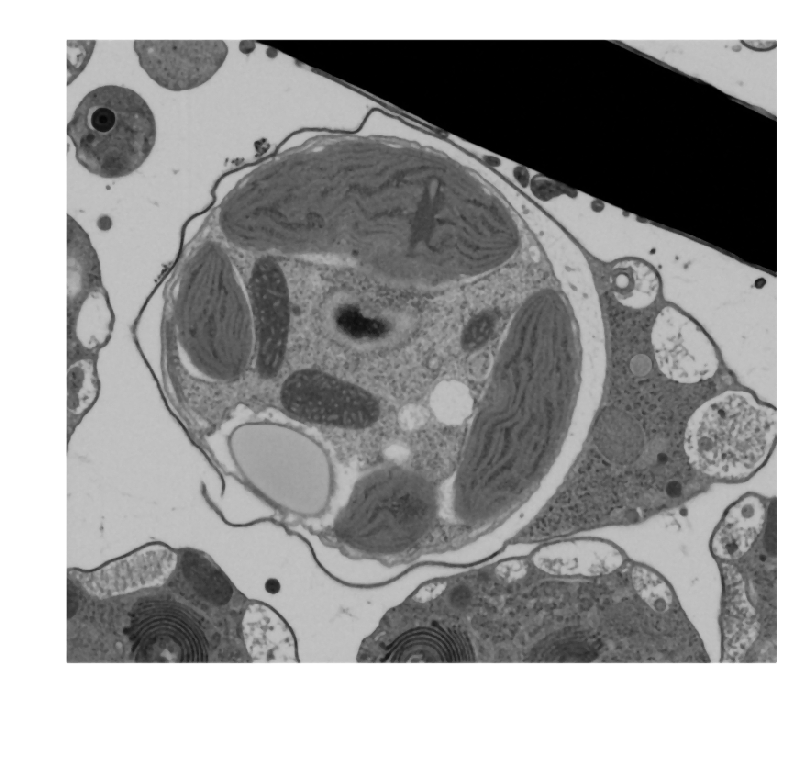

Actual z-index: 248Sampling: sampled from 492 source slicesScale: 10 x 10 x 10 nmContrast: source uint8. 8-bit source planes are written directly without intensity renormalization.Frame cache: warming 0/96Keyboard: ←/→ step, Home/End jump.

96 cached planes from 492 source slices. Cache size: 0.024 GiB. Source dtype: uint8.